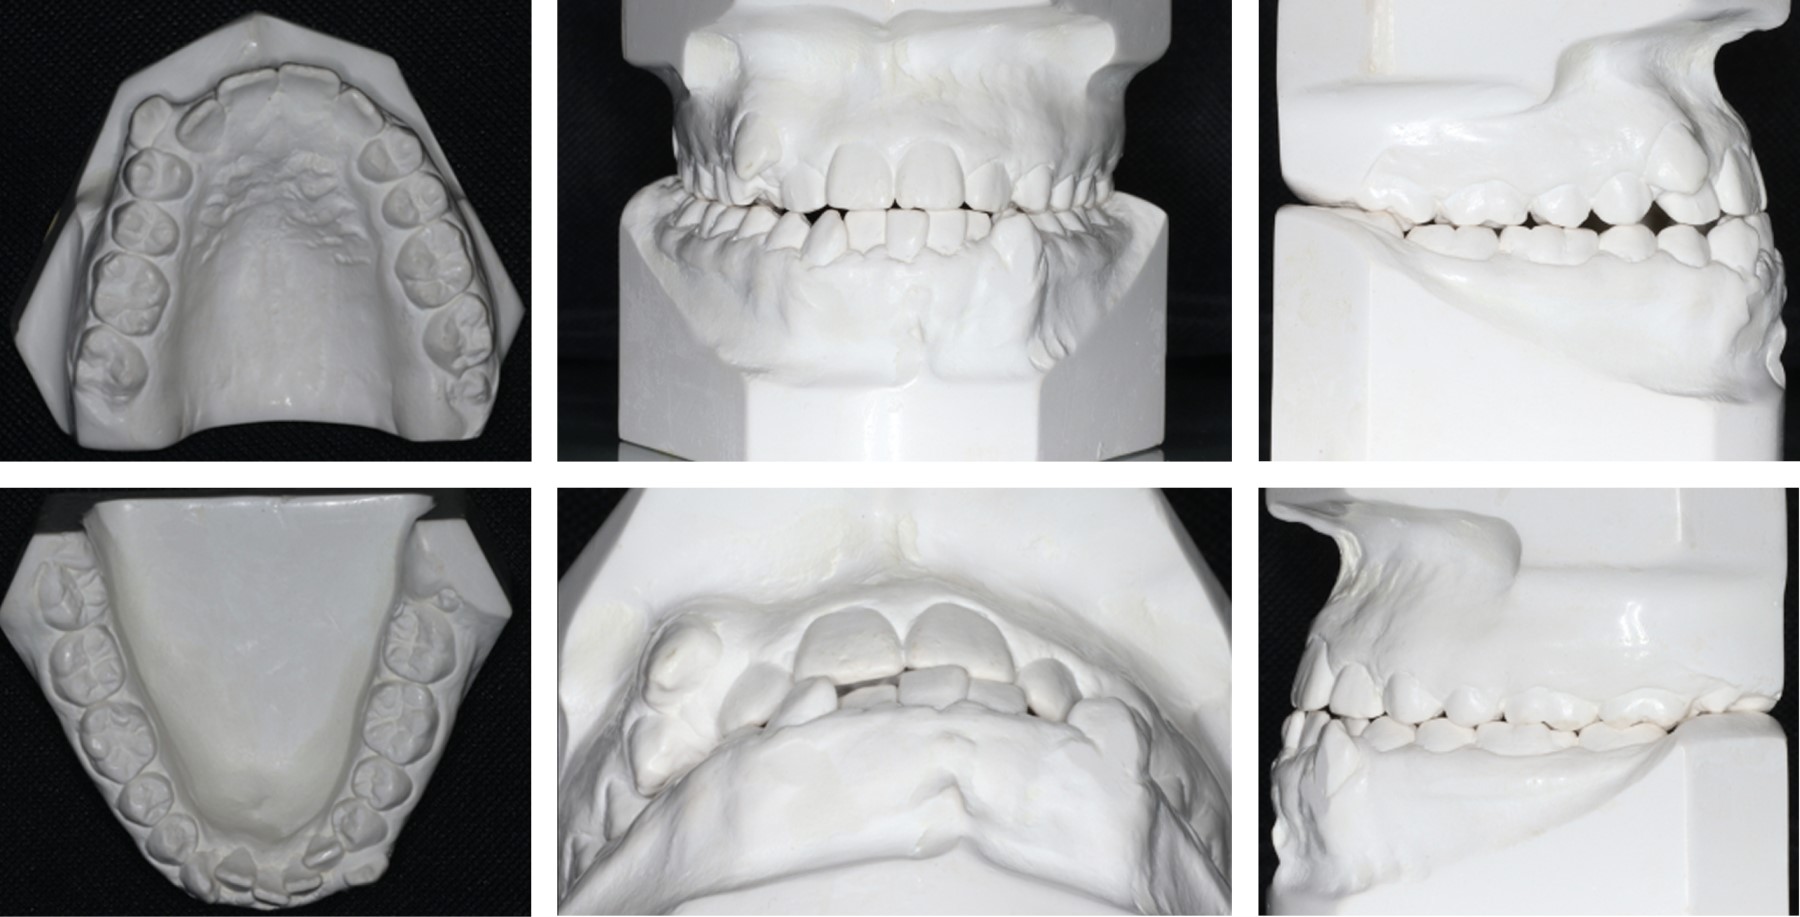

A 17-year-old female patient came to the Department of Dental Clinics of the University of Guadalajara for a check-up and was referred to the Orthodontics Clinic, with the consultation reason "I want my teeth and fangs to be well-aligned". She does not present pathological clinical data of any systemic alteration or TMJ dysfunction. Frontal esthetic analysis: the patient presents a long and oval face, with a dolichofacial biotype, paranasal region, and malar projection deficient, facial midline deviated to the right, enlarged middle and lower third, enlarged left internal fifth, and gingival smile. Profile analysis: the concave profile, due to a combination of maxillary hypoplasia and prognathism with unilateral mandibular laterognathia. Vertical: dolichocephalic pattern. Transverse: mandibular laterognathia to the right (Figure 1A and B), asymmetric condyles (left side wider) (Figure 2). Skeletal, anteroposterior: class III due to maxillary hypoplasia and mandibular prognathism (Figure 3). Dental: crown-root ratio 1:2, class III right molar, class I left molar, canine class not established (retained upper left canine), severe upper and lower crowding, bilateral posterior edge-to-edge bite, lower midline deviated to the left 4 mm, upper and lower oval arch form, horizontal and vertical overbite of 0 mm, presence of lower and upper third molars, no signs of periodontal disease (Figures 2 and 3). Functional: no alteration present.

According to the evaluation of the radiographic studies (Figure 3), extraoral and intraoral photographs (Figure 1), and cephalometric results (Table 1), interdisciplinary orthodontic-surgical treatment was performed to achieve the planned objectives.